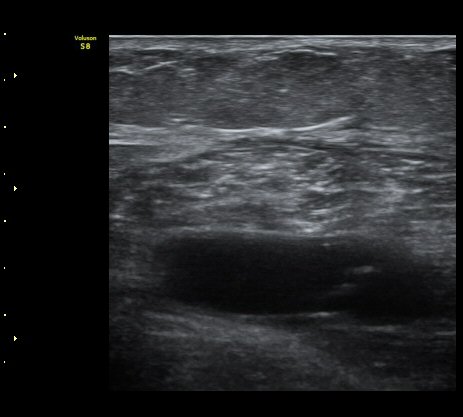

¿Ü°ß »ó ÀåµýÁö ºÎÁ¾ÀÌ °üÂûµÇ°í ³»Ãø ºñº¹±Ù¿¡ ±¹¼ÒÀû ¾ÐÅëÀ» º¸ÀÓ.

³»Ãøºñº¹±Ù°ú °¡Àڹ̱٠»çÀ̰¡ ¹ú¾îÁö°í ¼ö¾×ÀÌ Àú·ùµÊ.

ÃÊÀ½ÆÄ À¯µµÇÏ ¼ö¾× ÈíÀÎ(÷ºÎ µ¿¿µ»ó) ÈÄ ¾Ð¹ÚºØ´ë °íÁ¤.

³»Ãø ºñº¹±Ù ÆÄ¿Àº ´ë°³ ±Þ¼ºÀ¸·Î ¹ß»ýÇÏ¿© °æÇèÀÌ ÀÖ´Â ÀÇ»ç´Â ºñº¹±ÙÆÄ¿À» ÃßÁ¤ÇÒ ¼ö ÀÖ´Ù.

±×·¯³ª °æ¹ÌÇÑ ÆÄ¿ ÈÄ ¹«¸®ÇÑ ¿îµ¿À¸·Î ÆÄ¿ÀÌ ÁøÇàµÇ´Â °æ¿ì ÅëÁõÀÌ Å©Áö ¾Ê°í º´·Âµµ ¶Ñ·ÈÇÏÁö ¾Ê¾Æ

ºñº¹±Ù ÆÄ¿À» ÃßÁ¤ÇϱⰡ ½±Áö ¾Ê´Ù. ÀÌ·± °æ¿ì¿¡´Â È®Áø¿¡ ÃÊÀ½ÆÄ°Ë»ç°¡ ÇʼöÀûÀÌ´Ù.